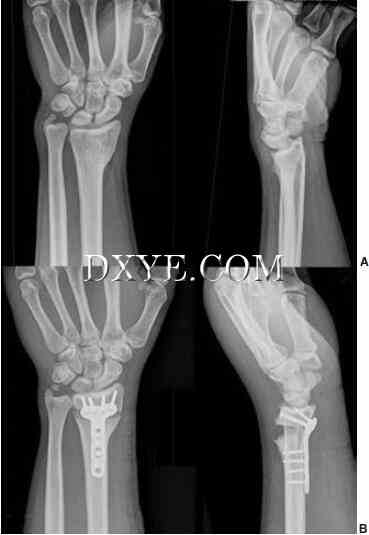

外部固定。外固定器通过将骨折固定到长度并中和骨折部位的压缩,弯曲和扭转力来起作用。对于高度不稳定的骨折伴显著干骺端粉碎的患者,外固定是有用的,因为它们可以使关节面与桡骨干对齐(图76.14)。然而,它们不能用于减少移位的关节内骨折。此技术在感染风险高或明显水肿排除安全切开复位内固定(ORIF)的情况下也是有用的。它通常与K线一起用于其他形式的固定。许多不同类型的外固定器框架可用于不同的针位置,不同的平面刚度,调整骨折复位的能力,以及固定器框架是否跨越桡腕关节(桥接与非桥接)。在桥接外固定器时,一组销钉放置在第二掌骨中,另一组放在近端径向轴中,从而跨越桡腕关节。在非桥接的外固定器中,远侧的销钉组被放置在远侧桡骨的关节片段中。这种设计可以防止韧带过度僵硬和手腕固定。然而,大的和稳定的远端碎片对于放置销是必需的。外固定器框架的变体是经皮放置的背侧固定器板(桥板),其从桡骨骨干延伸至第二或第三掌骨。这种“固定器 - 内部”在多发伤患者中特别有用,因为外固定使护理困难。

图 76.14.  外固定结合经皮穿针置入多发创伤患者,桡骨远端粉碎性骨折(AO C3型)。